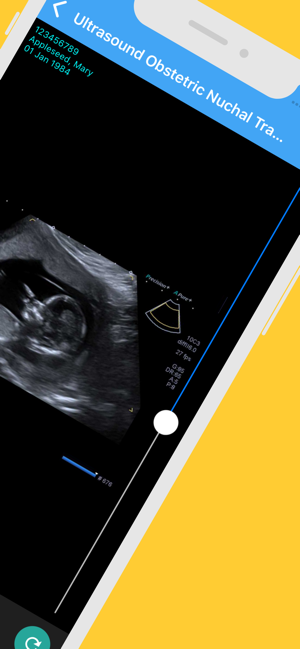

· access your images and reports (after your scan)

Once you have an account you can log in at any time to see your images and your reports. Your reports will be uploaded 14 days after we have authorised and sent the report to your referring doctor.